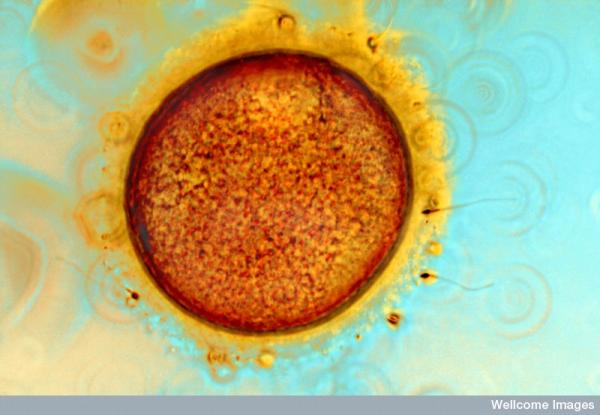

– Her konkurrerer forskere og medisinske fotografer om hvem som har produsert, ikke bare om det mest vitenskaplige bildet, men også det mest slående bildet. Vakre farger, fine former og lekker komposisjon verdsettes, med den begrunnelse at dette er viktig i kommunikasjonen til offentligheten. Samtidig holder det ikke at bildet er fascinerende, det må også argumenteres for at det er nyttig, forteller Johansen. –Her spiller nok også bildets symbolverdi inn, slik som når et bilde av egg- og sædceller fra kunstig befruktning blir til et symbol på livets mysterium.

– Vi har en tendens til å anta at idet legene kan observere og lokalisere sykdom og helseplager, så kan de også behandle og kurere det. Selv om dette kan gjelde ved tilfeller hvor man brekker et bein eller får hjelp til assistert befruktning, er det ikke alltid slik. Vitenskapelig bildeteknologi viser fram veldig mye som vitenskapsfolk likevel ikke forstår og mestrer, sier Johansen.